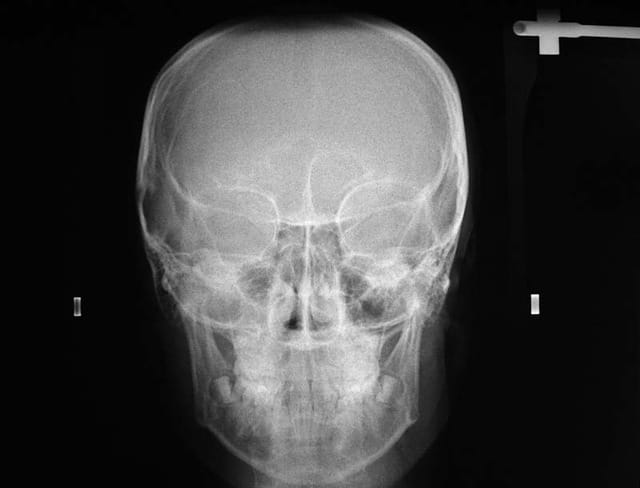

25/06/2009 à 13h57

complément Rx. demandés

@+ Bjc.